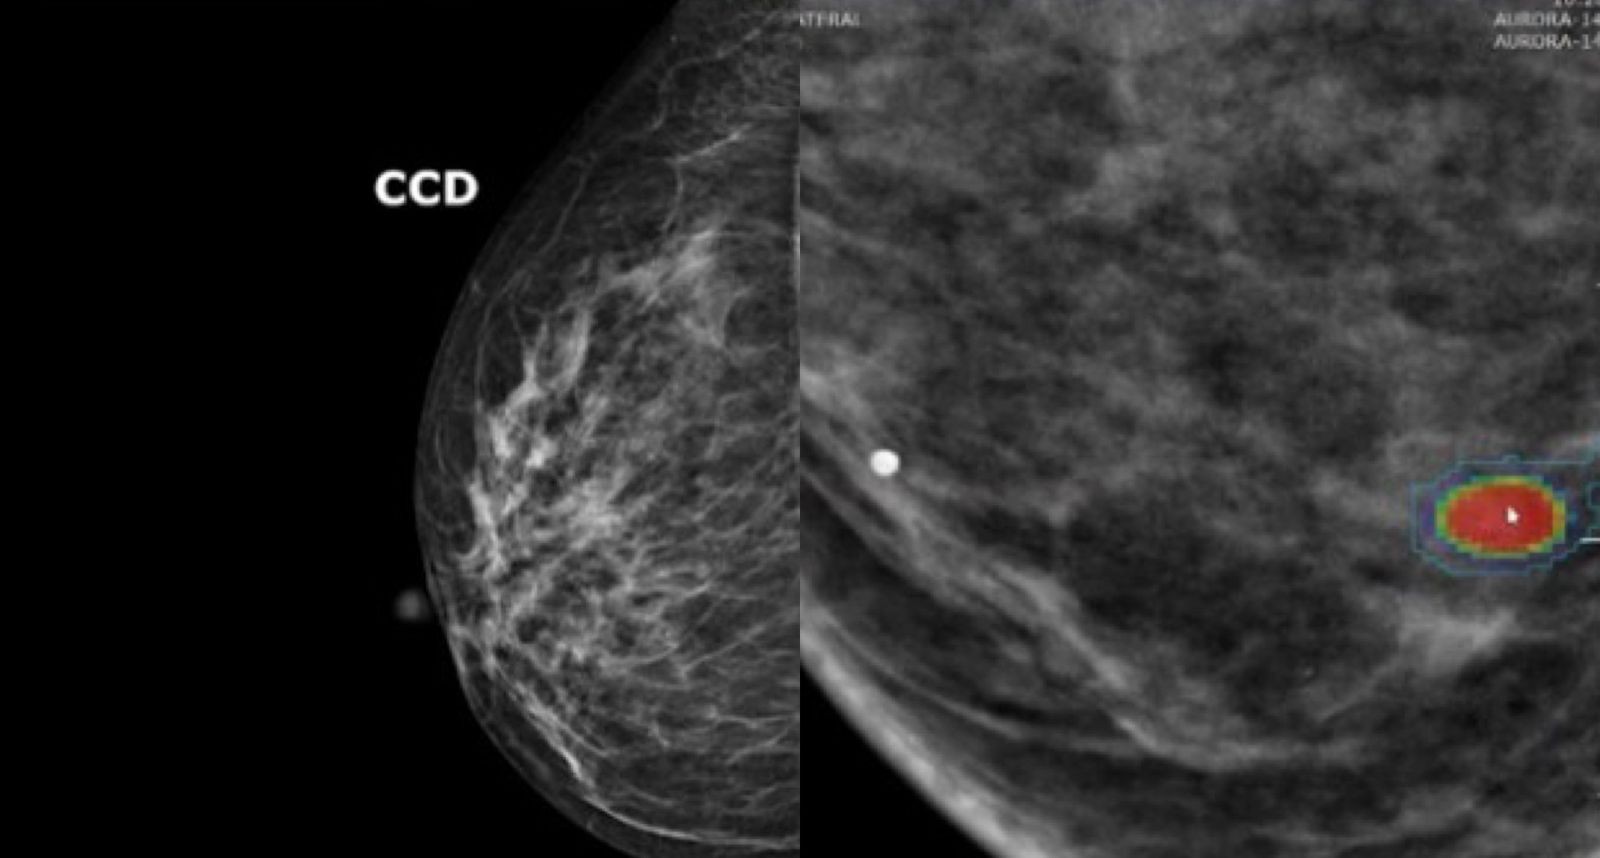

O motivo é que muitos casos de câncer de mama não são detectamos por meio da mamografia, pelo menos não em estágio inicial. Kuhl explica que em particular tumores agressivos e de crescimento rápido muitas vezes não são visíveis nas mamografias. São justamente esses tumores que matam muitas mulheres.

Agora um novo algoritmo promete reorientar a triagem: um modelo de inteligência artificial (IA) consegue avaliar com elevada precisão, simplesmente analisando dados de imagens de mamografia, o risco de uma pessoa desenvolver câncer de mama nos próximos cinco anos.

Por isso, Kuhl defende o rastreamento individualizado do câncer de mama. Afinal, a precisão da mamografia também varia significativamente de mulher para mulher: quanto mais denso o tecido mamário, maior o risco de desenvolver a doença – e pior a identificação pela mamografia. Muitas mulheres não sabem disso, conta a médica.

Para identificar quais mulheres precisam de uma RM para detecção precoce, o Consórcio Clairity (uma cooperação internacional de 46 instituições de pesquisa nos EUA, Canadá, América do Sul e Alemanha) desenvolveu o sistema de inteligência artificial Clairity Breast, que foi treinado com centenas de milhares de mamografias das Américas e da Europa.

Ao contrário dos modelos de risco tradicionais, o algoritmo não requer informações sobre histórico familiar, genética ou estilo de vida. Ele calcula a probabilidade de câncer de mama exclusivamente a partir da mamografia e categoriza as mulheres em grupos de risco com base em limiares definidos.

A IA reconhece não apenas a quantidade de tecido glandular, mas também sua textura, o que é outro parâmetro para o risco de câncer de mama. “Apenas cerca de 10% das mulheres têm esse tecido glandular extremamente denso. A grande maioria das que desenvolvem câncer de mama e recebem um diagnóstico tardio têm tecido menos denso”, afirma Kuhl.

Porém, Kuhl diz que simplesmente reduzir a idade de rastreamento não é muito eficaz. Em vez disso, ela defende uma abordagem em duas etapas. “Primeiro, mamografia para detecção precoce; em seguida, uma análise por IA deve ser realizada para determinar o risco de desenvolvimento da doença nos próximos cinco anos.”

Se o algoritmo indicar um risco particularmente alto, uma ressonância magnética deve ser oferecida, e a mamografia deixa de ser necessária para essas mulheres.